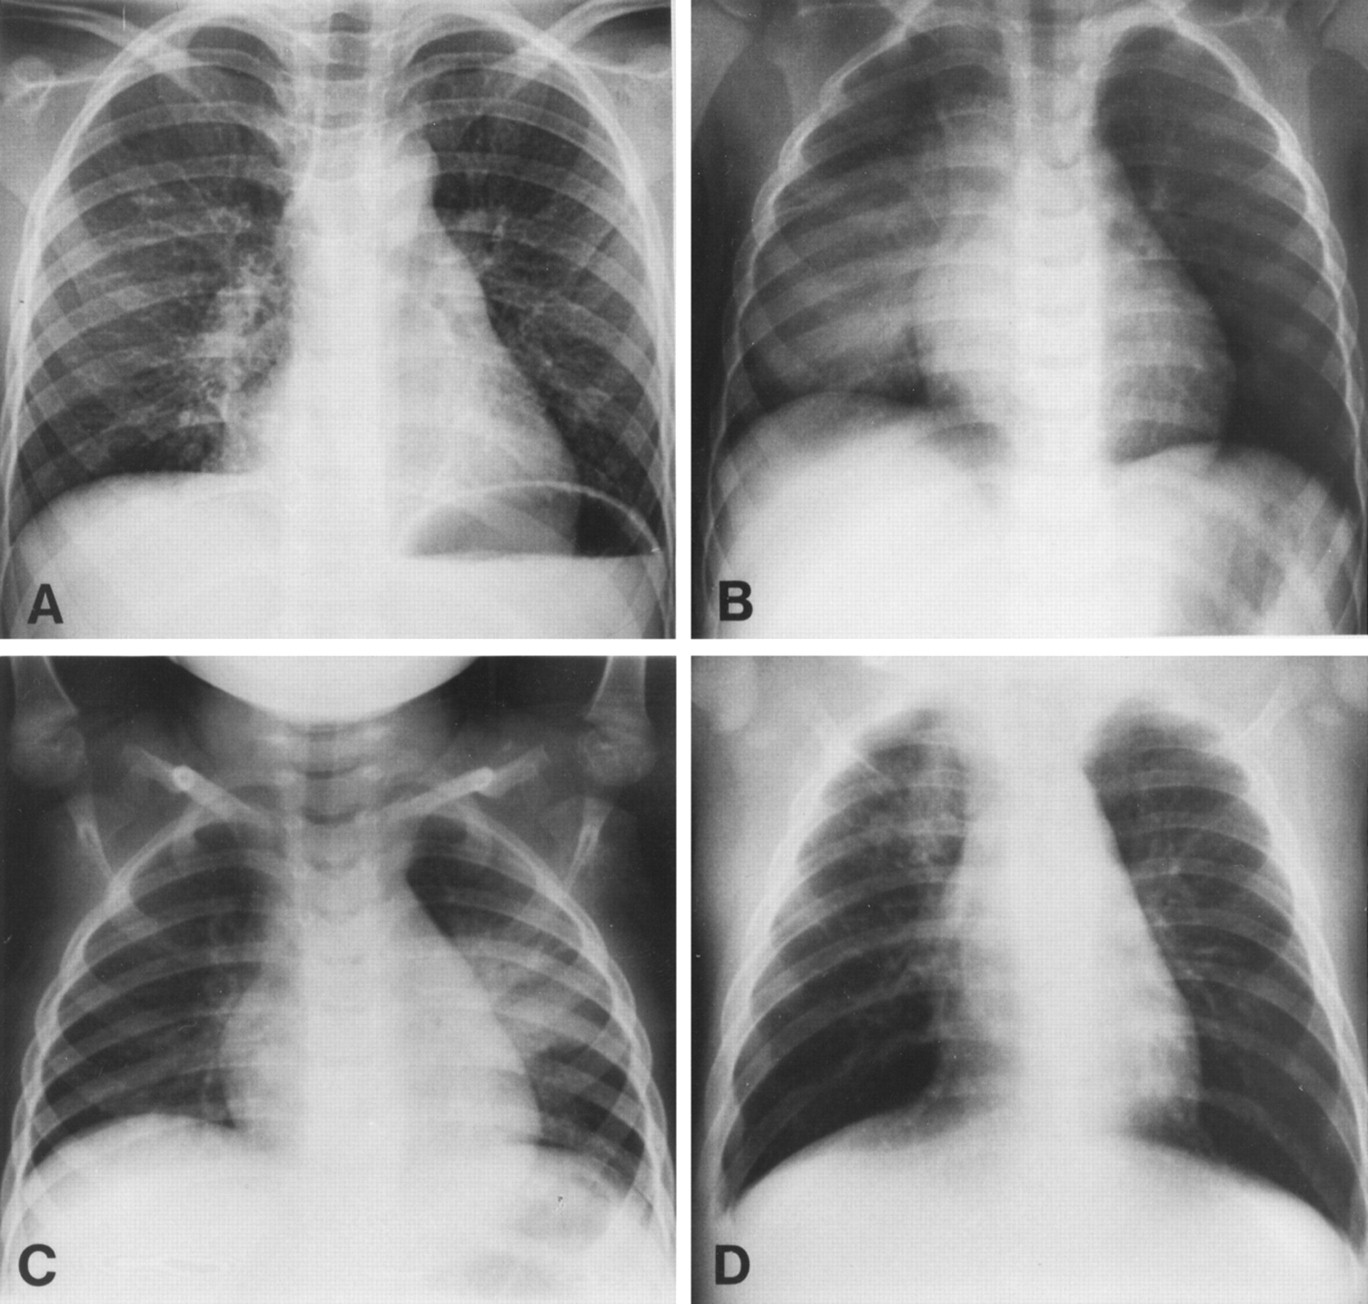

Diagnostic tests help by identifying whether the infection affects lung tissue, airways or general immunity. Chest X-rays, sputum tests and oxygen measurements provide clear evidence for lung involvement. According to our editor’s research, chest X-rays reveal fluid, inflammation or consolidation common in pneumonia. Viral infections often show normal imaging results because tissue remains structurally intact. Blood tests also indicate whether bacterial processes are likely. These tools guide appropriate treatment choices and prevent overuse of antibiotics. Diagnostic clarity improves safety and outcomes. Testing transforms uncertainty into actionable understanding.